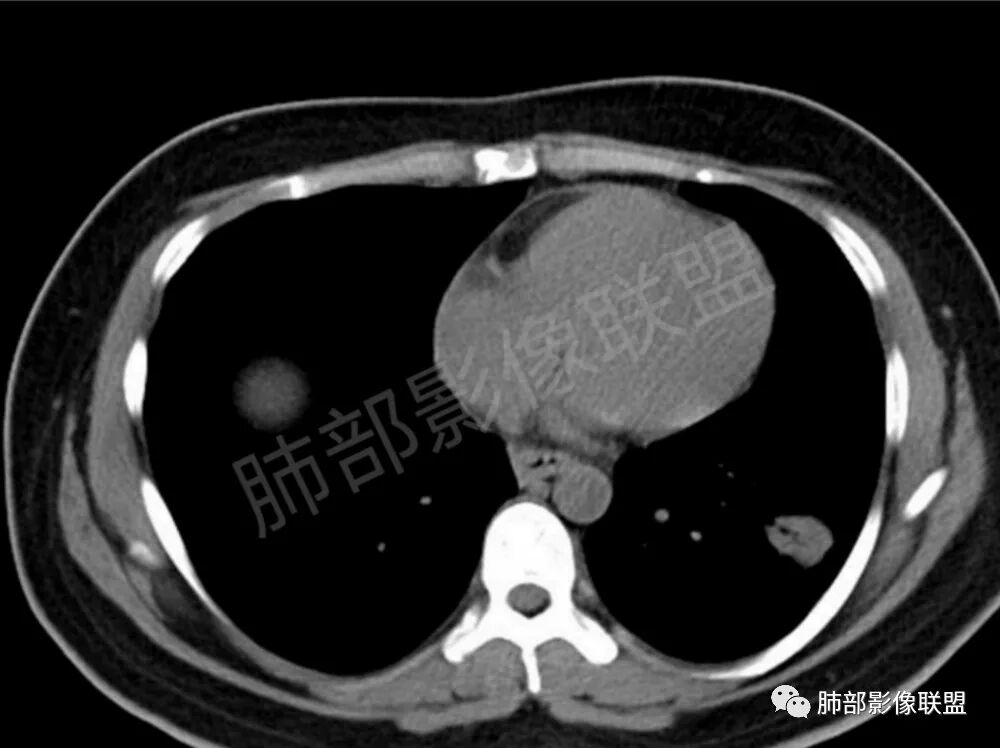

两肺多发结节性,大部分位于胸膜下,部分结节周围可见晕征。局部结节内可见扩张的支气管,纵隔淋巴结大,脾大,22岁男,HIV阳性,常规先考虑隐球菌。鉴别淋巴瘤,结核,马儿。

男,22,半年前咳嗽伴少痰,查HIV阳性,痰查TB阳性,既往有肺部斑片影伴空洞、纵隔淋巴结肿大、脾大。SCC、CA50、CA199、FER增高,此次胸部CT:两肺多发结节影,部分沿血管束分布,部分贴胸膜下,大小不一,密度不一,部分较散、边缘模糊,部分较实、圆钝、周围模糊晕,部分结节有支气管进入穿行自然,部分结节有血管分支自如通过。考虑HI∨相关淋巴增殖类病变,淋巴瘤?LYG?鉴别PC、TB。

青年男性,半年前咳嗽,HIV阳性,结核DNA阳性,肿标糖类抗原和铁蛋白增高。外院影像有纵隔淋巴结增大伴脾大,肺部病灶空洞。现在影像:肺内多发沿支气管分布(有支气管充气征,长轴沿支气管分布)及胸膜下分布(平行于胸膜)的大小不等结节,个别伴有空洞,双侧腋窝淋巴结肿大。纵隔图片不够,是否还有淋巴结肿大未知,脾脏未显示。

1、HIV相关淋巴瘤,有HIV阳性,有纵隔及腋窝淋巴结肿大,肺内病灶沿支气管分布(中轴淋巴间质)及胸膜下分布(周围淋巴间质),有脾大,这个是必须要考虑的。但是原来的影像是肺斑片影伴空洞,又有疑问,需要穿刺明确。

影像学缺乏特征性,以支气管血管周围、胸膜下及双肺下叶周边多发结节影最多见,结节易坏死形成空洞,伴有游走性和多变性的特征,结节周围可有磨玻璃样晕征,有时也可见单发结节影、薄壁的囊状阴影或弥漫性浸润影。肺门、纵隔淋巴结肿大少见, 可见胸腔积液和气胸。